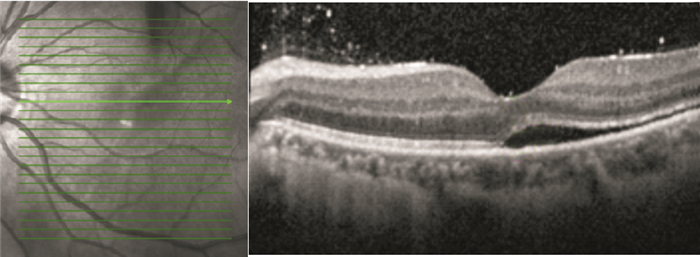

手術后1、3、6、12個月,BCVA 1.0者分別為1、8、11、15只眼。手術后6個月BCVA 0.15~1.0,平均BCVA0.59±0.29;手術后12個月,BCVA 0.15~1.0,平均BCVA 0.65±0.28。手術后6、12個月平均BCVA比較,差異無統計學意義(t=-0.636, P=0.529)。手術后12個月,視網膜下液吸收者BCVA 0.3~1.0,平均BCVA 0.68±0.34。其中,視網膜微結構正常者0.86±0.14;神經上皮層黃斑囊樣水腫者0.52±0.12;IS/OS斷裂者0.55±0.08;IS/OS和ELM斷裂者0.44±0.11。視網膜下液殘留者BCVA 0.15~1.0,平均BCVA 0.57±0.40,其中,BCVA 1.0者2只眼(圖 3)。視網膜微結構正常者、神經上皮層黃斑囊樣水腫者、IS/OS斷裂者、IS/OS和ELM斷裂者之間平均BCVA比較,差異有統計學意義(F=52.42,P<0.05)。視網膜下液殘留者平均BCVA與視網膜下液吸收者之間比較,差異有統計學意義(t=-5.747, P=0.000)。

手術后1、3、6、12個月,BCVA 1.0者分別為1、8、11、15只眼。手術后6個月BCVA 0.15~1.0,平均BCVA0.59±0.29;手術后12個月,BCVA 0.15~1.0,平均BCVA 0.65±0.28。手術后6、12個月平均BCVA比較,差異無統計學意義(t=-0.636, P=0.529)。手術后12個月,視網膜下液吸收者BCVA 0.3~1.0,平均BCVA 0.68±0.34。其中,視網膜微結構正常者0.86±0.14;神經上皮層黃斑囊樣水腫者0.52±0.12;IS/OS斷裂者0.55±0.08;IS/OS和ELM斷裂者0.44±0.11。視網膜下液殘留者BCVA 0.15~1.0,平均BCVA 0.57±0.40,其中,BCVA 1.0者2只眼(圖 3)。視網膜微結構正常者、神經上皮層黃斑囊樣水腫者、IS/OS斷裂者、IS/OS和ELM斷裂者之間平均BCVA比較,差異有統計學意義(F=52.42,P<0.05)。視網膜下液殘留者平均BCVA與視網膜下液吸收者之間比較,差異有統計學意義(t=-5.747, P=0.000)。

圖3

患眼手術后6個月OCT像。視網膜下仍存在積液

圖3

患眼手術后6個月OCT像。視網膜下仍存在積液

本組患者手術后2周,雙目檢眼鏡聯合B型超聲檢查見視網膜復位;OCT檢查提示視網膜下仍有部分積液,直至手術后12個月,視網膜復位率亦未達到100%。分析其主要原因,OCT分辨率較B型超聲高近10倍,可獲得10 μm的高分辨率,能更清楚的顯示視網膜各層結構,發現微小異常。手術后12個月OCT檢查示視網膜下液吸收率為88.1%,與Wolfensberger和Gonvers[2]報道的手術后1年11.0%的患者殘存黃斑下積液的發生率相當。有文獻報道,影響視力預后的主要因素有視網膜脫離時間、神經上皮層囊樣水腫、視網膜下液殘留、IS/OS損傷及ELM破壞[3]。視網膜脫離時間影響手術后視力的恢復已成為共識[1, 4, 5],但黃斑積液對視力的影響尚無定論[6]。Wakabayashi等[7]認為黃斑積液對手術后視力無明顯影響,而本組患者手術后12個月,黃斑處視網膜積液明顯影響手術后視力。其原因主要是黃斑下積液導致視網膜神經層和視網膜色素上皮(RPE)層之間的物質轉運發生障礙。及時發現并手術,視力預后較好;積液時間過長,光感受器細胞外節的代謝受影響,視力預后差。